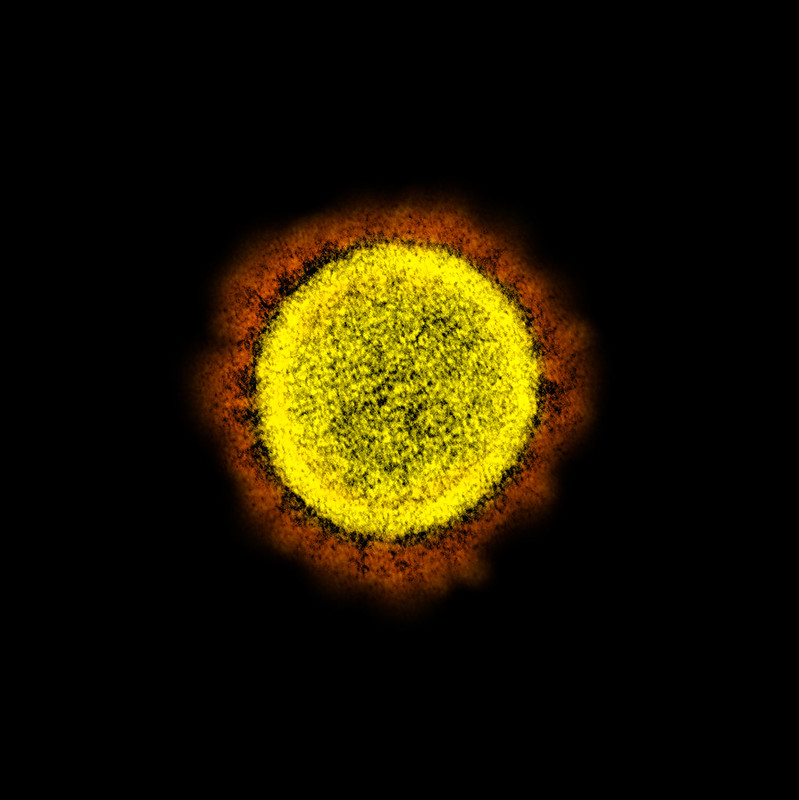

![]() Is the desire to evade antibody response an evolutionary factor for viral spike density?

Is the desire to evade antibody response an evolutionary factor for viral spike density?

Sars-Cov-2 (diameter) 120nm #spikes 65 density 0.15